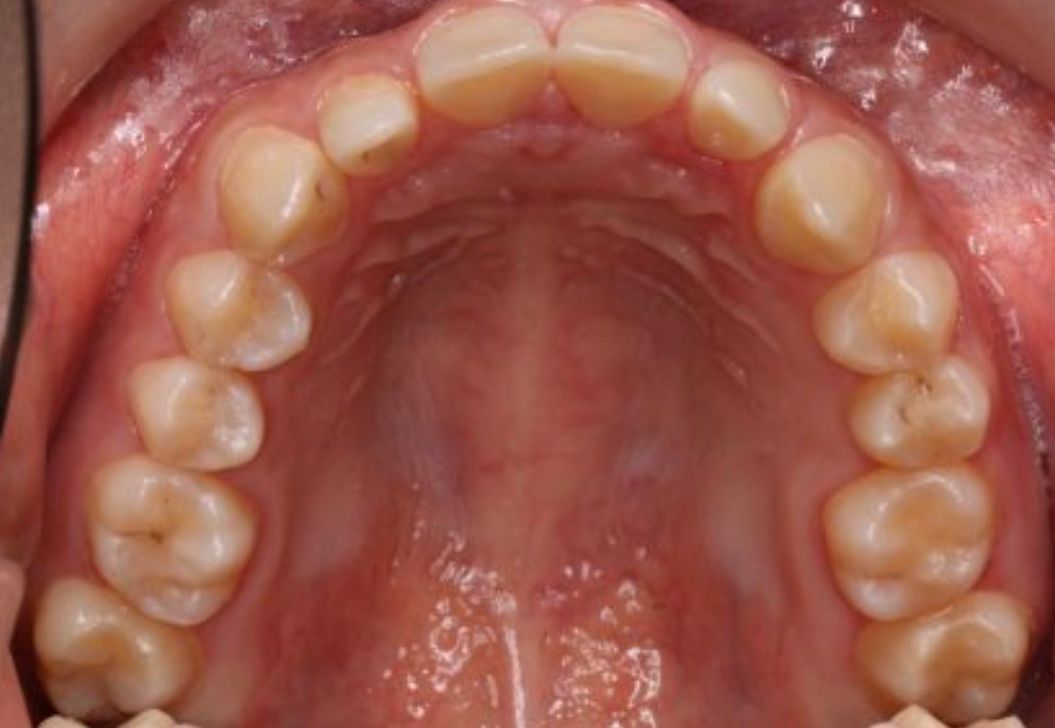

Fotos y videos